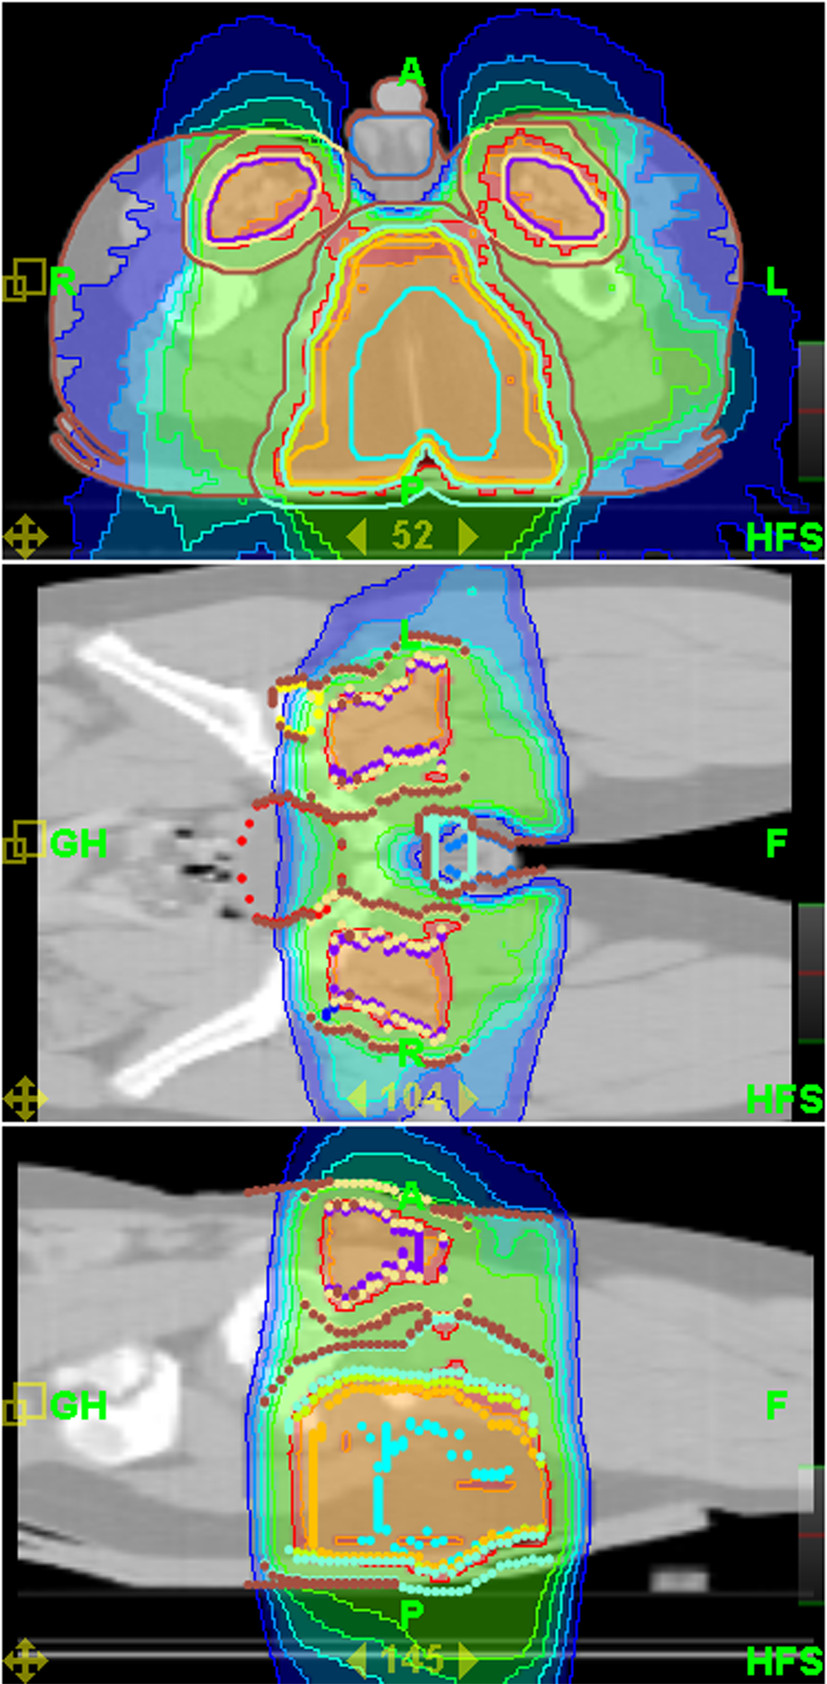

Mean coverage index for entire group of patients and all PTVs was 0,82 ± 0,13. Mean homogeneity index was 1,07 ± 0,02. Mean PTV doses, coverage and homogeneity indexes for selected challenging cases or groups of patients are presented in Table 3. Even for challenging cases of craniospinal irradiation and extended thoracic and abdominal volumes irradiation coverage and homogeneity of delivered dose were acceptable. Mean doses for selected OARs are presented in Table 4. It shows that substantial sparing of critical structures was achieved in all patients although major variability in OARs mean doses in this very heterogeneous patient population is evident. In Figures 2 and 3 examples of treatment plan for medulloblastoma and perineal rhabdomyosarcoma with metastases to inguinal nodes are presented.

Figure 2 Thumb

Figure 2. Dose distribution for craniospinal irradiation.